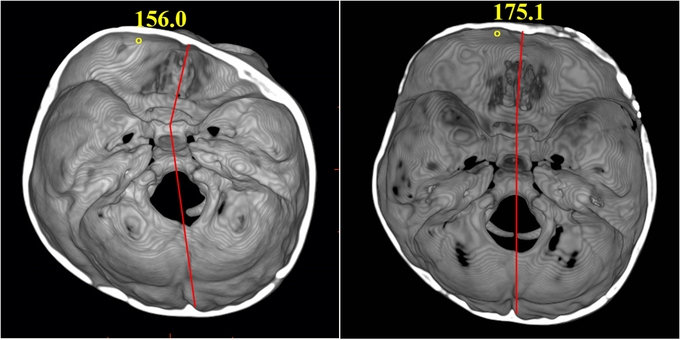

특히 무엇보다도 수술 직후부터 외적 비대칭이 개선될 뿐 아니라, 뇌 기저부의 비대칭까지 교정되어 10년 이상 장기추적결과 아이가 성장한 이후로도 얼굴뼈가 대칭적으로 발달한 것을 확인했다.

신연기를 이용한 두개골 성형술은 환아의 머리뼈를 조각내지 않고, 유합된 두개골의 봉합선만 일부 절개한다. 절개한 봉합선에 신연기를 장착한다. 이후 보호자가 하루에 0.5~1.5mm씩 신연기를 돌린다. 신연기 조절을 통해 절개된 뼈 부위가 조금씩 벌어져 그 틈에 새로운 뼈가 생기게 되는 방법이다. 정상 범위만큼 뼈가 성장한 이후 신연기를 제거하는 수술까지 진행하면 치료가 마무리된다.